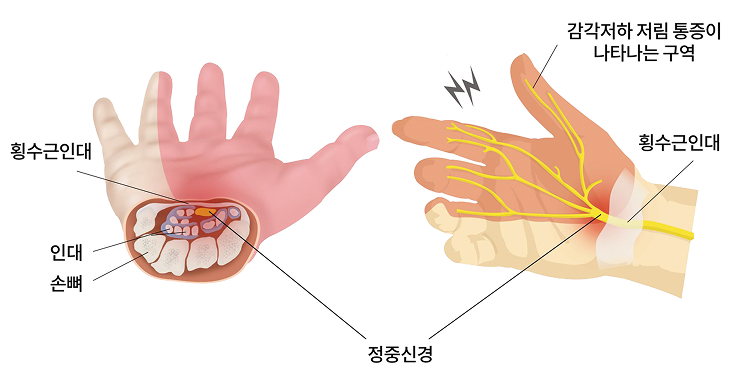

정식명칭은 수근관 증후군이라 하는데 손목 앞쪽의 작은 통로인 수근관이 좁아져 이곳을

통과하는 정중신경이 눌려지며 통증 및 저림 증상이 나타나는 병증입니다.